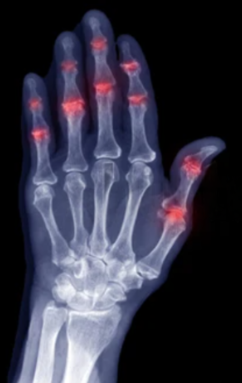

Doenças inflamatórias, como artrite reumatoide

O diagnóstico da lesão dos tendões flexores da mão é clínico, baseado em exame físico e histórico do paciente. O especialista pode solicitar exames complementares, como:

Ultrassonografia da mão: avalia integridade dos tendões

Ressonância magnética: indicada em casos mais complexos